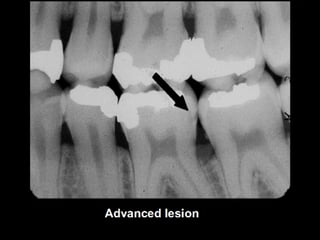

Dental caries is an irreversible microbial disease that causes demineralization and destruction of tooth structure, often leading to cavitation. It is classified based on anatomical site as occusal, smooth surface, or root caries. Inter proximal caries specifically refers to caries between teeth, which can be detected via bite-wing x-rays for low or moderate risk patients. Proper dental care and hygiene is important to prevent recurrent caries.